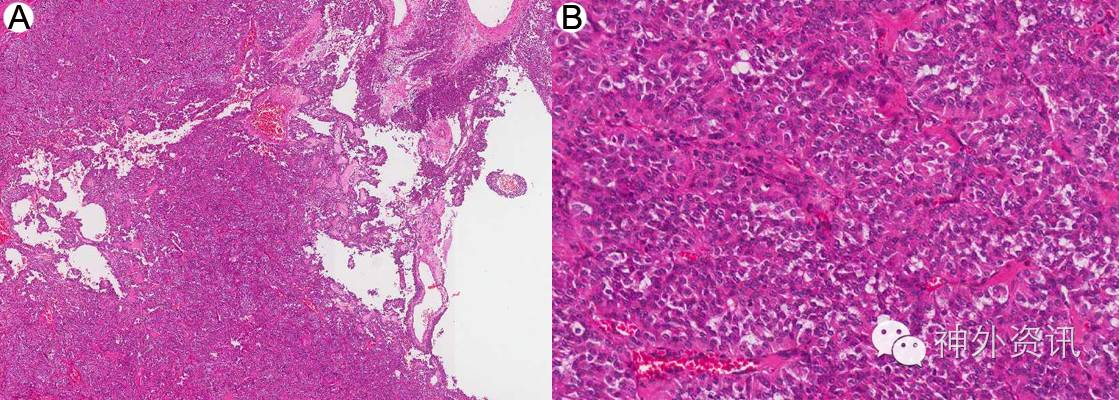

术后常规病理及免疫组化,报告为椎管内神经内分泌肿瘤,考虑转移性可能(图3)。免疫组化结果:S-100局部 +,GFAP-,Syn+,CgA+, CD56+, Vimentin+, NSE+, CAM5.2+, EMA -,Ki-67 10-20%,NF -, inhibin-, CD10-(图4)。

图3. 椎管内神经内分泌肿瘤,HE染色:A. 低倍镜下显示为囊实性上皮样肿瘤 B.肿瘤呈细胞球样结构,富于血管,染色质均匀细颗粒状。

图4. 免疫组化结果: A.CGA弥漫阳性 B.SYN弥漫阳性 C.CAM5.2弥漫强阳性 D.CK(AE1 AE3)弱阳性。